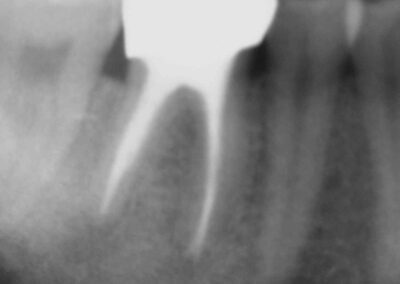

Und zum Abschluss noch eine schöne Doublette:

Galerie: